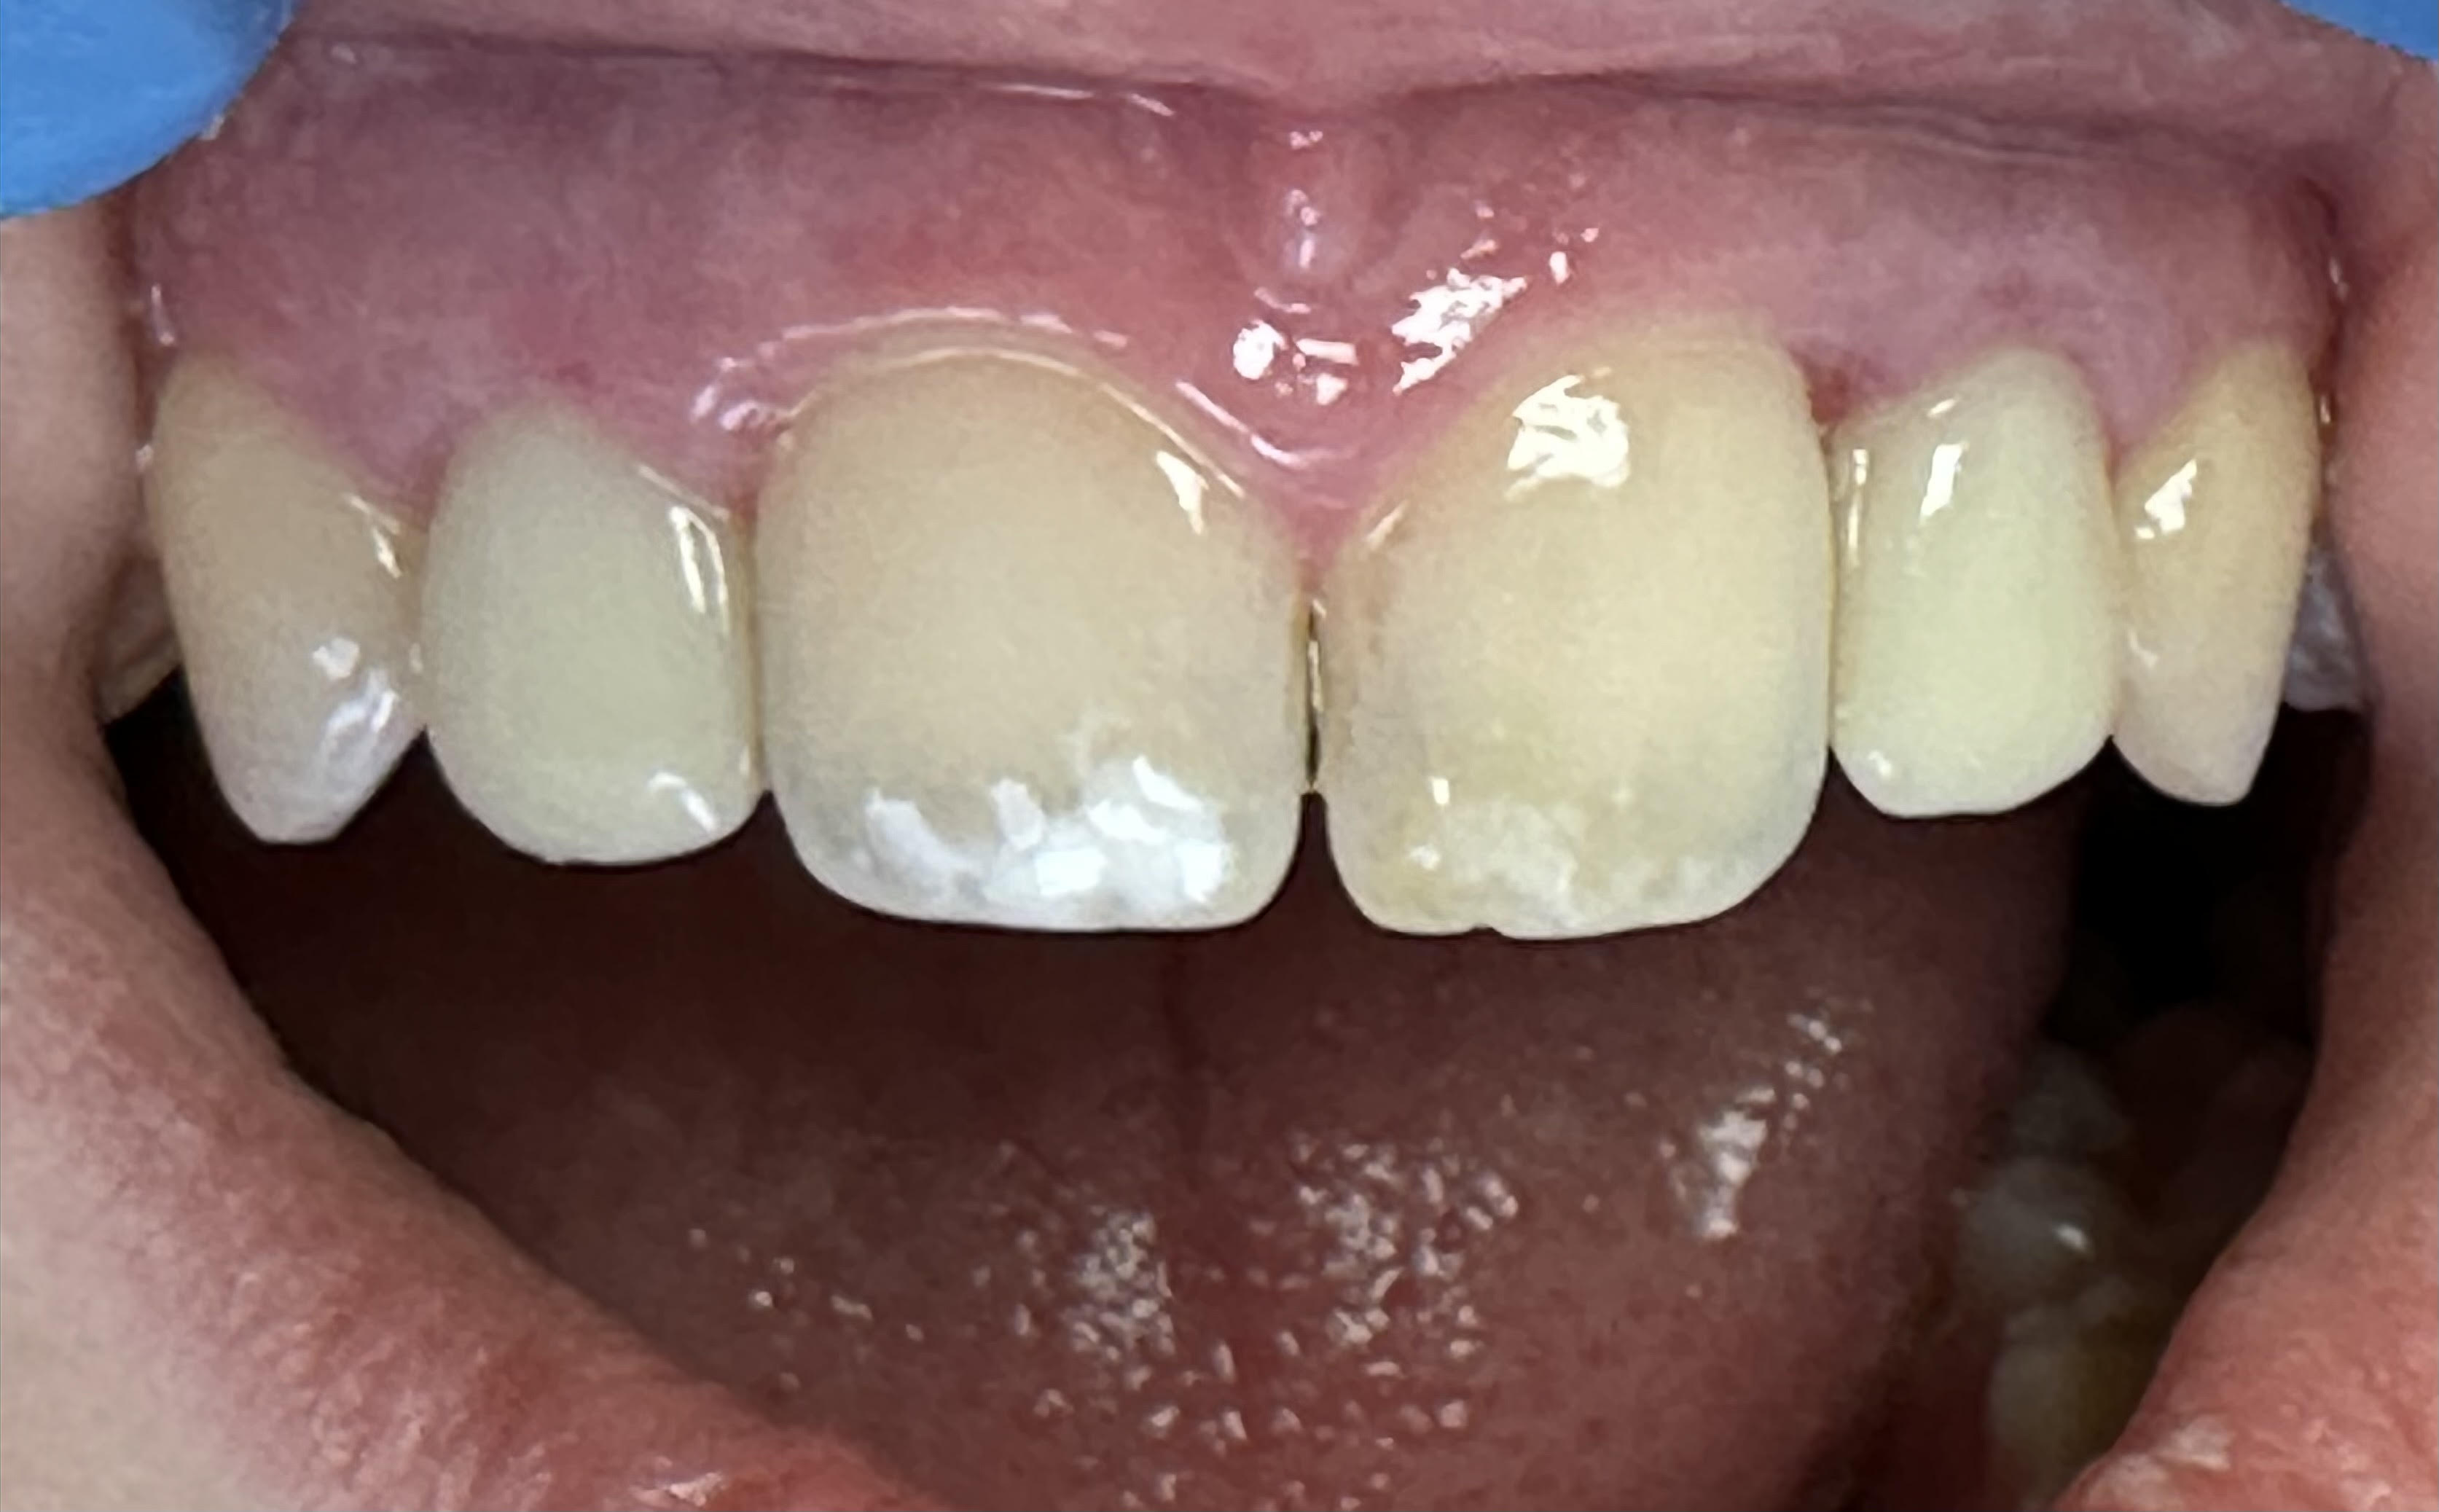

Case Study: Dental Implant

A patient with a missing tooth received a dental implant, restoring both function and aesthetics.